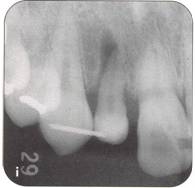

Fi 545e45f g 5-2i The recipient site right before transplant procedure (2 weeks after extraction of the first molar). |

|